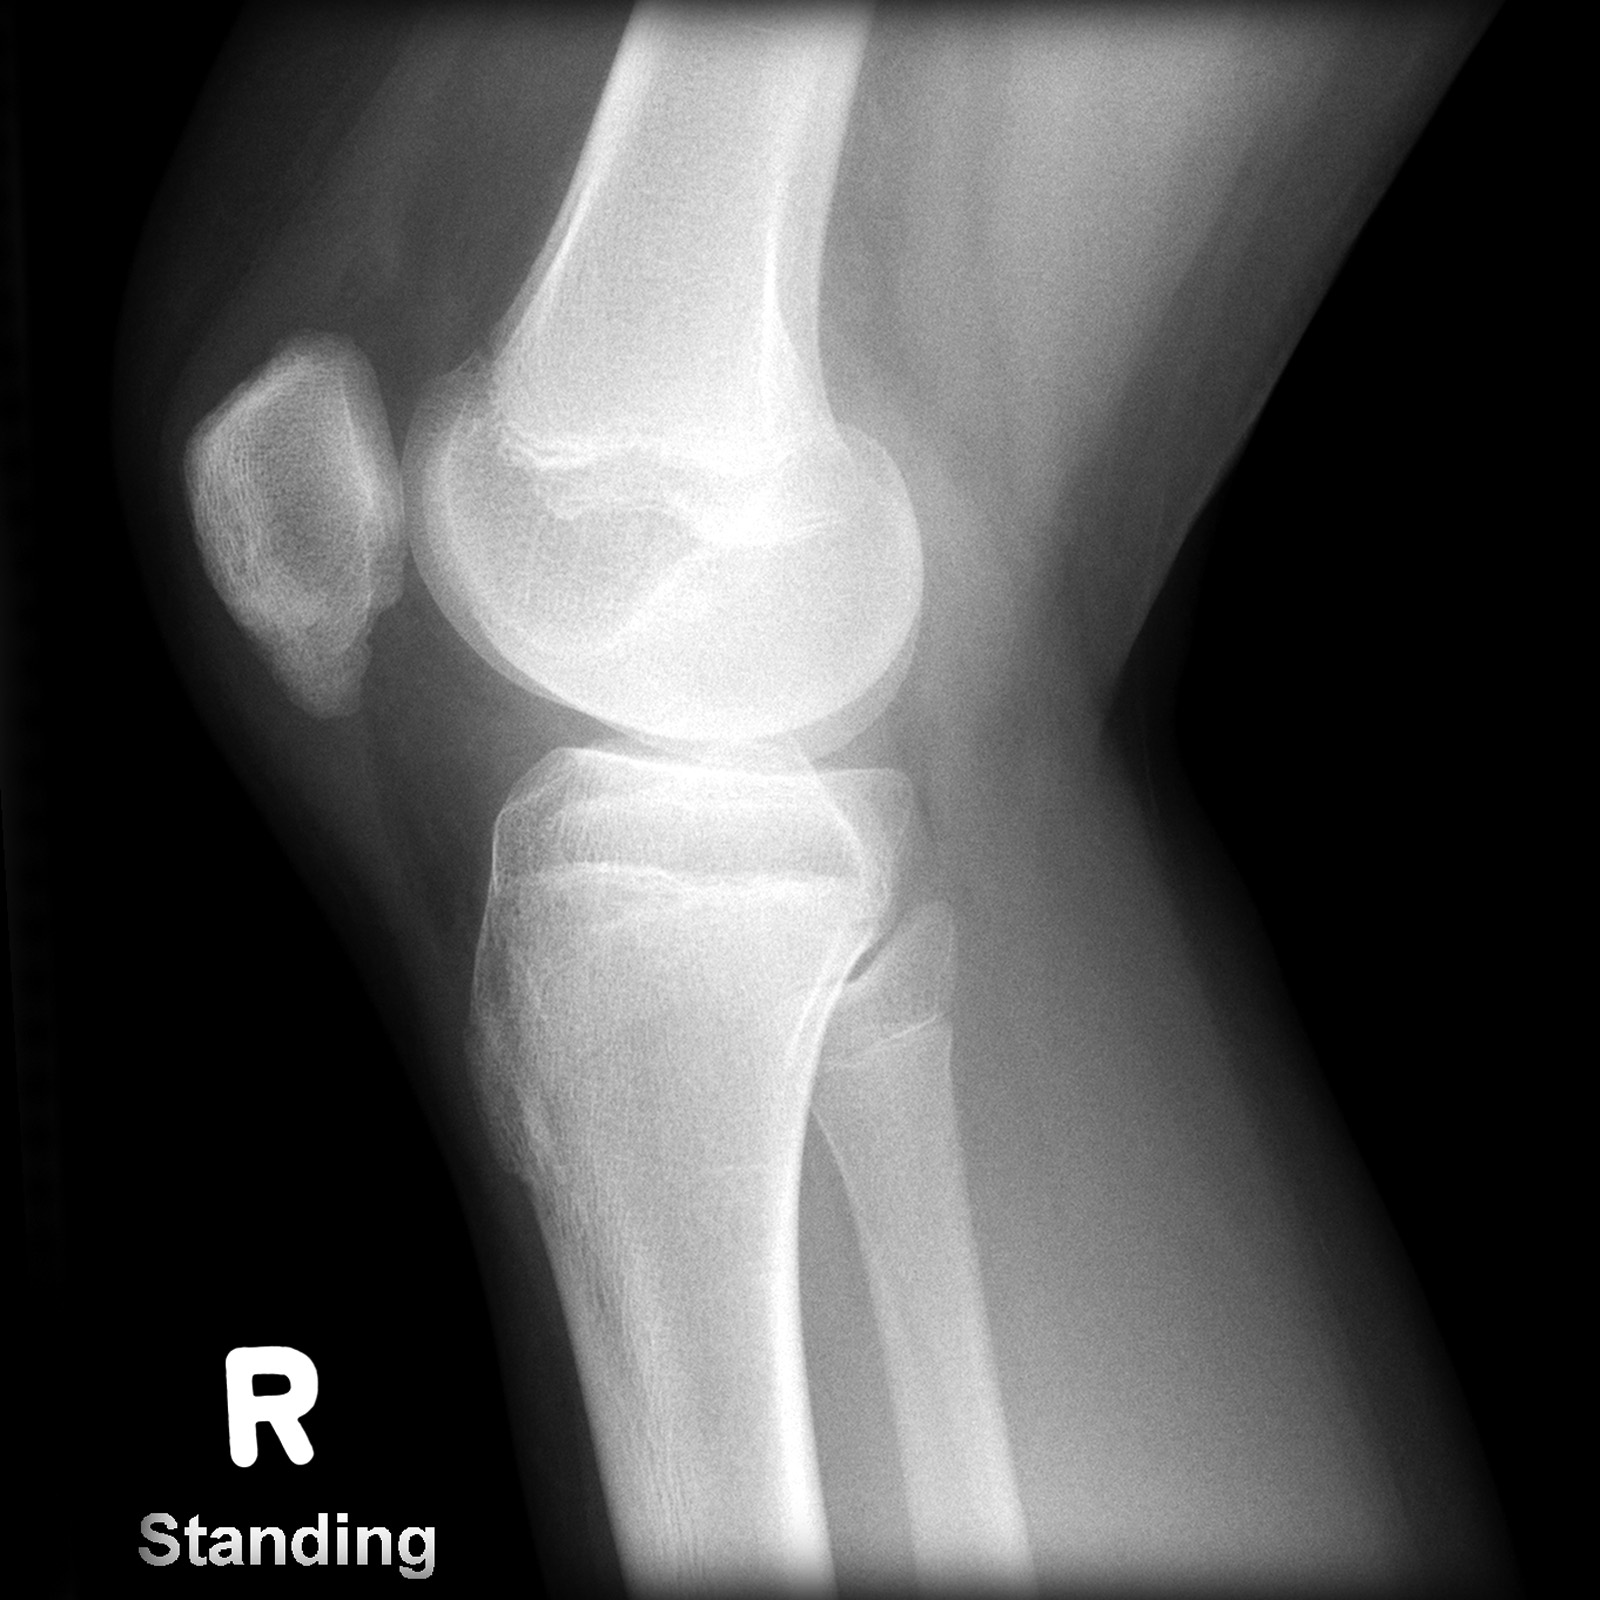

Ларсена йохансона

Ларсена йохансона 146 фото